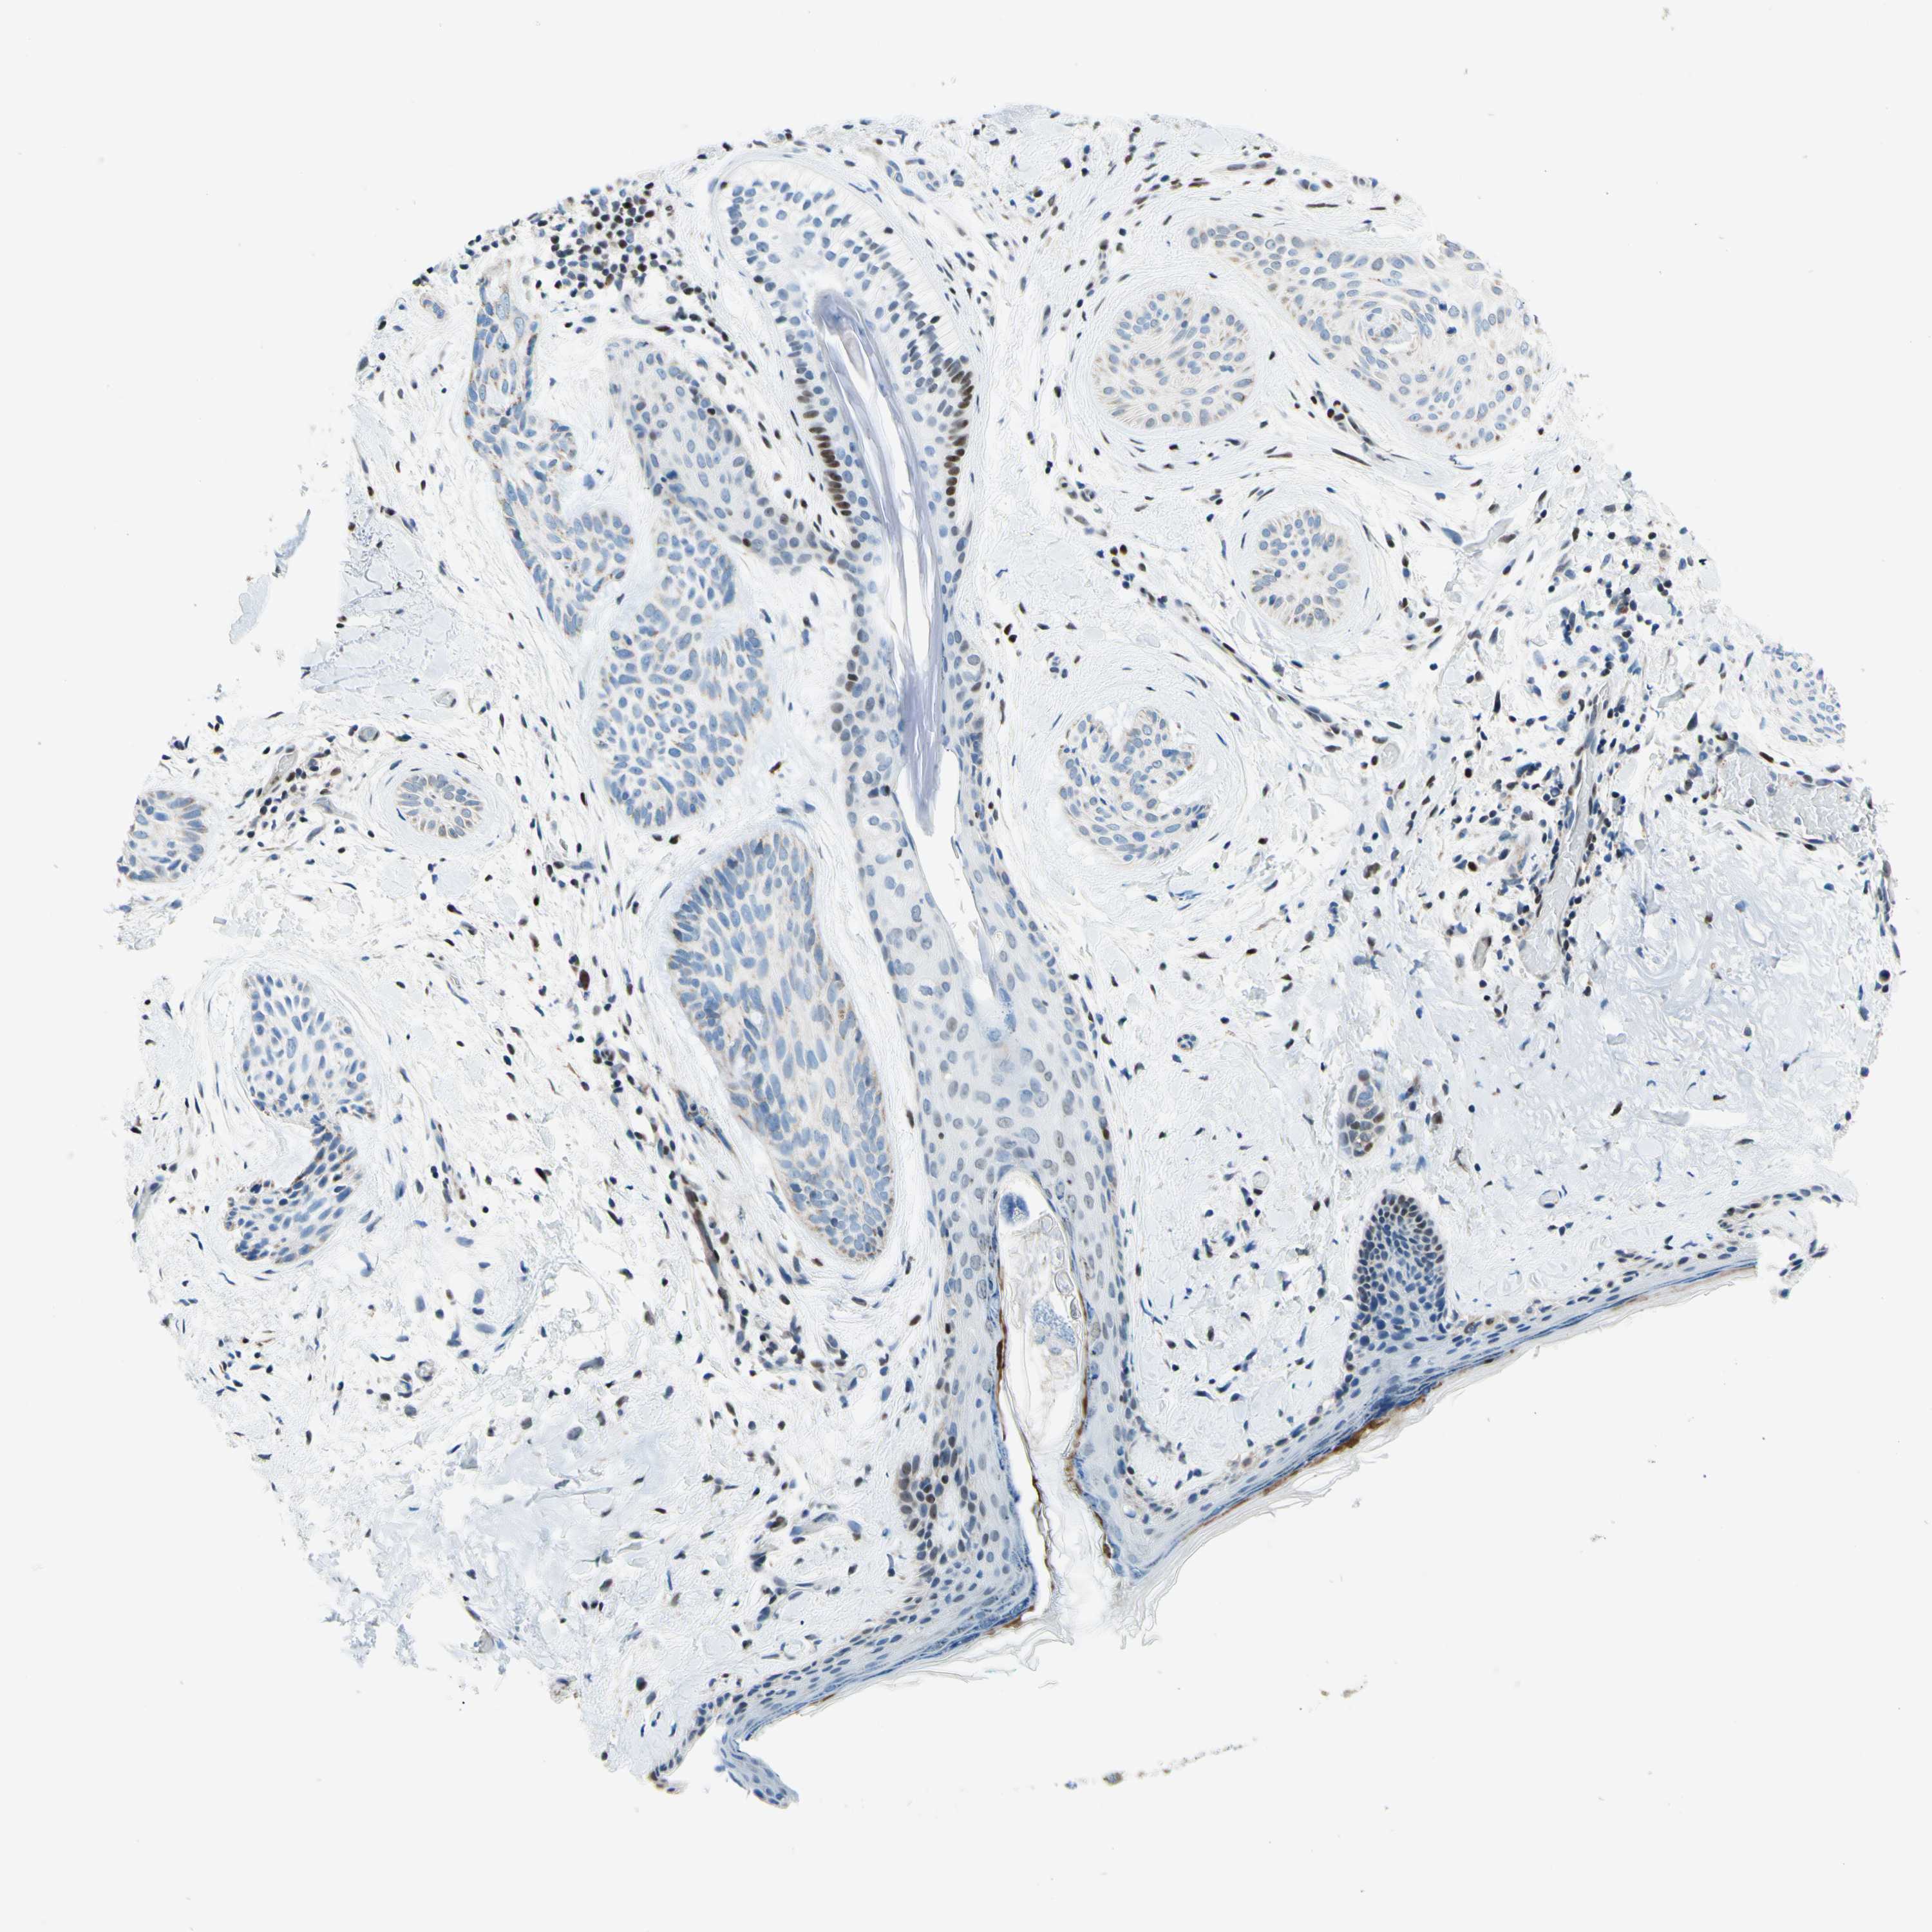

Basal cell and squamous cell cancer

SKIN CANCER - Protein expressioni

A mouse-over function shows sample information and annotation data. Click on an image to view it in a full screen mode. Samples can be filtered based on level of antibody staining by selecting one or several of the following categories: high, medium, low and not detected. The assay and annotation is described here.

Each image is clickable and will lead to virtual microscopy that enables deeper exploration of all samples and also displays staining intensity scores, fraction scores and subcellular localization as well as patient and tissue information for each sample.

Antibody HPA048677

Staining

High

Medium

Low

Not detected

Intensity

Strong

Moderate

Weak

Negative

Quantity

>75%

75%-25%

<25%

None

Location

Nuclear

Cytoplasmic/membranous

Cytoplasmic/membranous,nuclear

Basal cell carcinoma